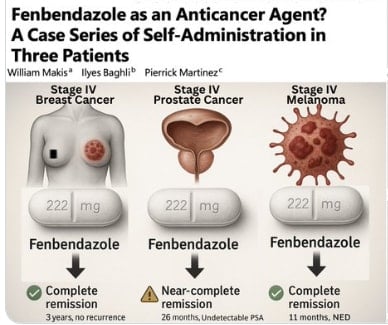

Mayo Clinic Proceedings dergisinde yayımlanan çarpıcı bir vaka serisi, veteriner hekimlikte yaygın kullanılan fenbendazol ilacının insan kanser tedavisinde beklenmedik başarı gösterdiğini ortaya koydu. Kemoterapi almayan üç ileri evre kanser hastasında tümör yükü dramatik şekilde azaldı ve uzun süreli tam remisyon yani kanser hücreleri yok edildi. Mayo Clinic’te yayınlanan makaleye göre tedavi olan hastaların öyküsünü gözler önüne serdi. İşte o hastalar…

83 yaşındaki bir kadının karaciğeri kanser doluydu, doktorlar “birkaç hafta ömrü var” dedi. Diğer hasta ise 75 yaşında bir erkek kemikleri un ufalanmıştı, yürüyemiyordu. 63 yaşındaki adam melanomdan ölüm raporunu bekliyordu. Üçü de doktorların tavsiyesi ile fenbendazola başladı. Günlük 222 mg’lık kedi ilacıyla birkaç ayda mucize yaşadılar. İlaç kullanımı sonrası hastaların kanser belirteleri sıfırlandı, PET-CT’ler tertemiz çıktı, ölüm haberi beklenen hastalar tekrar hayata döndü!

Kedilerin parazit ilacı Fenbendazol, ileri evre kanserlerde tam remisyon yani ortadan kaldırdı.

Mayo Clinic Proceedings’de yer alan makeleye göre çalışmada yer alan belgedeki insanlar ve hastalıkları;

– 83 yaşındaki kadın hasta: Metastatik meme kanseri (karaciğer, kemik, akciğer tutulumu). Günlük 222 mg fenbendazol tedavisiyle 6 ay içinde CA 27.29 tümör belirteci normal sınırlara indi, PET-CT’de aktif hastalık izlenmedi. 3 yıldır remisyonda.

– 75 yaşındaki erkek hasta: Metastatik prostat kanseri (yaygın kemik tutulumu). 222-444 mg/gün fenbendazol + androjen deprivasyon tedavisiyle PSA değeri tespit edilemez seviyeye düştü. 26 ayda kemik lezyonlarında belirgin gerileme gözlendi.

– 63 yaşındaki erkek hasta: BRAF-mutant metastatik melanom. Fenbendazol tedavisi sonrası dolaşımdaki tümör DNA’sı sıfırlandı. 11 ayda “hastalık belirtisi yok” durumu sağlandı.

Fenbendazolün etki mekanizması, mikrotübül polimerizasyonunu inhibe etmesi, glikoliz yolunu baskılaması ve p53-bağımlı apoptozu tetiklemesi olarak açıklanıyor. Preklinik çalışmalar da ilacın çeşitli kanser hücre hatlarında güçlü antineoplastik etki gösterdiğini destekliyor.

Bilim insanları yayımlanan makale sonrası Fenbendazol ile kanserin tedavisi hakkında oldukça iyimser konuştu; “Bu vakalar umut verici olsa da anekdotsaldır yani henüz bilimsel bir kanıtı yok. Spontan remisyon yani kendi kendine yok oldu denilemez buna eşlik eden tedavilerin katkısı göz ardı edilememeli. Mutlaka randomize yani rast gele kullanılmamalı kontrollü klinik araştırmalar yapılmalı.” uyarısında bulundular.